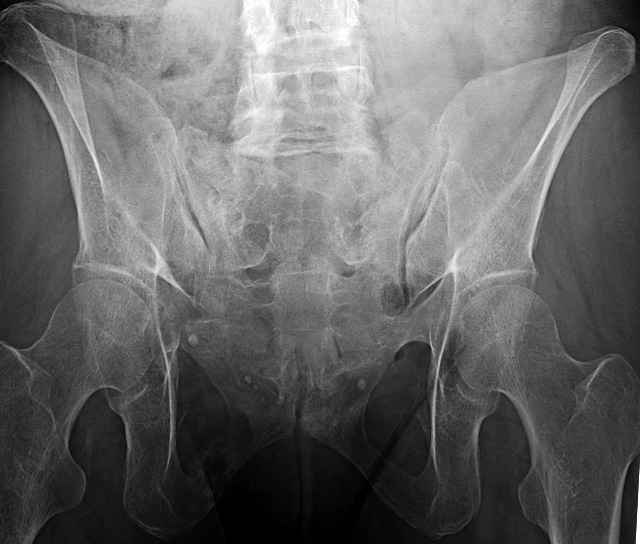

3 Months After Fall

Continued Pain & Immobility

(+) Instability to Compressive Manual Exam